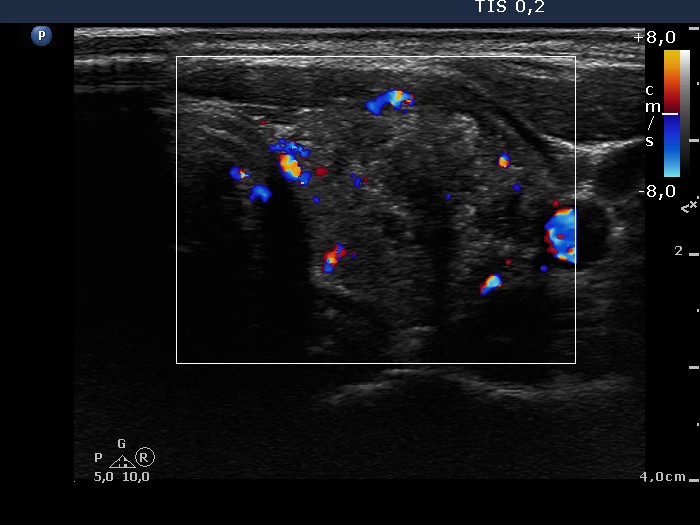

Ultrasonography: The thyroid was echonormal with a small insignificant moderately hypoechogenic lesion in the right lobe. There was a hypoechogenic nodule in the left lobe. The nodule contained numerous microcalcifications and coarse calcification, as well. The intranodular blood flow was a little bit increased. We found an enlarged lymph node in the left side of the neck.